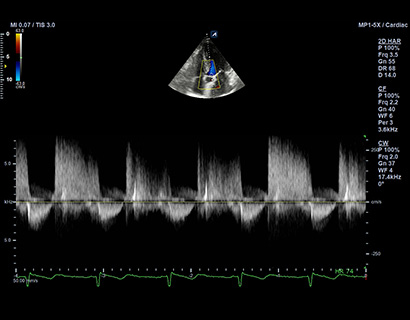

MP1-5X(NEW)

X+ Crystal Signature™ phased array (1~5MHz)

Application:

Cardiac, TCD, EM, Abdomen, Pediatric

CW5.0

Pencil type transducer (5.0MHz)

Application:

Cardiac

CW2.0

Pencil type transducer (2.0MHz)

Application:

Cardiac